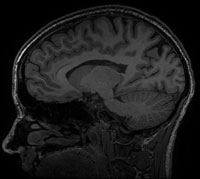

Structural MRI image